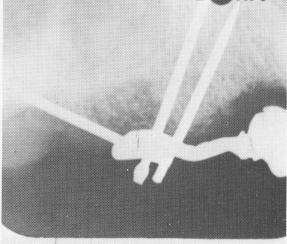

Fig. 10-179. Roentgenograms show the pins drilled through the template and the superstructure cemented over the pins.

When the cores hardened, they were prepared for full coverage restorations (Fig. 10-177). The superstructure was then fitted, adjusted, and cemented into position over the two acrylic cores and gold coping (Fig. 10-178). Fig. 10-179 shows the pins driven through the scalloped template and the superstructure cemented over the acrylic core and gold coping.